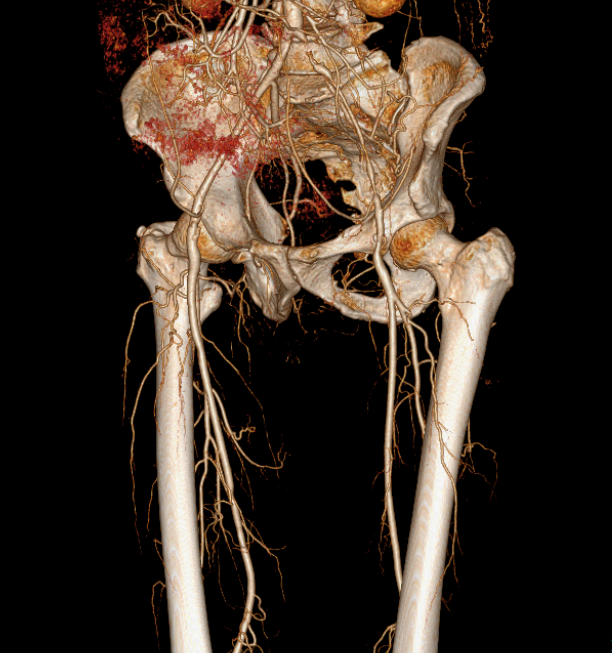

术前详解

(1)髂总动脉开口处病变,需要支架能够精准定位,既不能覆盖腹主动脉分叉型处遮挡对侧血流,又不能向髂总动脉内移牺牲有效锚定区。

(2)病变全长约115mm,预计覆盖血管全长约135mm。LCA=7.4mm,LEIA=5.7mm,要实现6mm到8mm的直径渐变。

(3)LIIA起始部重度狭窄,RIIA完好,双侧股深动脉,股浅动脉均正常。

影像1:术前测量及三维影像